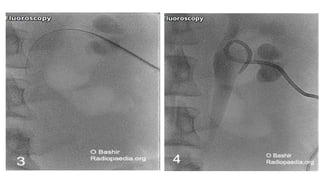

Equipment • USG orfluoroscopy guidance • LA 1% or 2% lignocaine • 18 gauge puncture needle • 0.035 inch stiff guidewire • Water soluble contrast media • Dilators • Pigtail drain (8 French)

• 8.